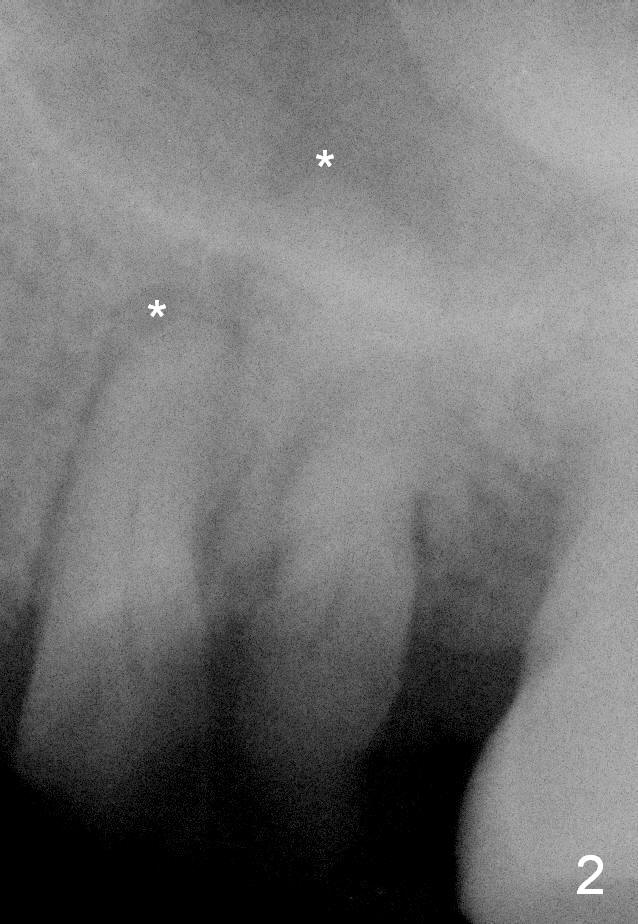

A 49-year-old man requests to restore #14 with residual roots (Fig.1). There is periapical radiolucency (Fig.2 *). A 5.9x10 mm bone-level implant is placed with minor sinus lift (Fig.3), whereas a short (Fig.4) or long (Fig.5) tissue-level implant is placed without or with sinus lift. The implant could be as large as 7 mm (Fig.5) to prevent post-extraction ridge atrophy.

It appears that the palatal root (Fig.6 P) is separated from the buccal ones (MB, DB). Connection between the latter appears to be weak (Fig.2) and could be broken using proximators or small straight elevator.